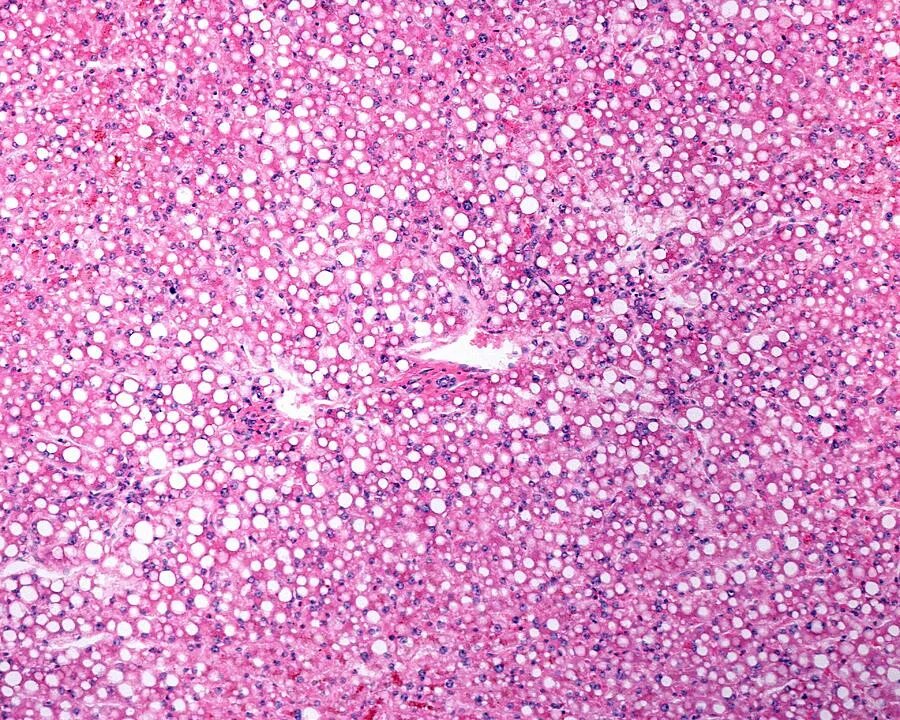

Липидоз печени